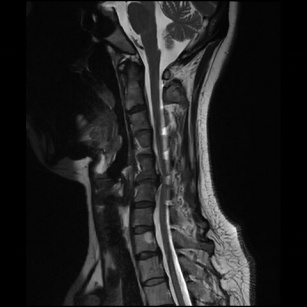

术前CT 术前MRI

近日,一名44岁女性患者由于近3个月来深受颈肩部不适困扰,同时伴有右上肢放射痛,严重影响日常生活,遂前往大场医院就诊。MRI检查结果显示:患者C56颈椎间盘突出,压迫脊髓及神经根,C5、C6锥体后缘骨赘增生,引发椎管狭窄。

入院后,脊柱外科陈建伟主任对患者进行了细致检查,并结合影像资料,明确诊断为颈椎病。考虑到患者年龄相对较轻,若采用保守治疗,存在脊髓、神经压迫进一步加重的风险。经过与患者充分沟通病情,在获得患者同意后,最终决定为其施行(空气/水介质)内镜辅助下颈椎前路减压融合术。